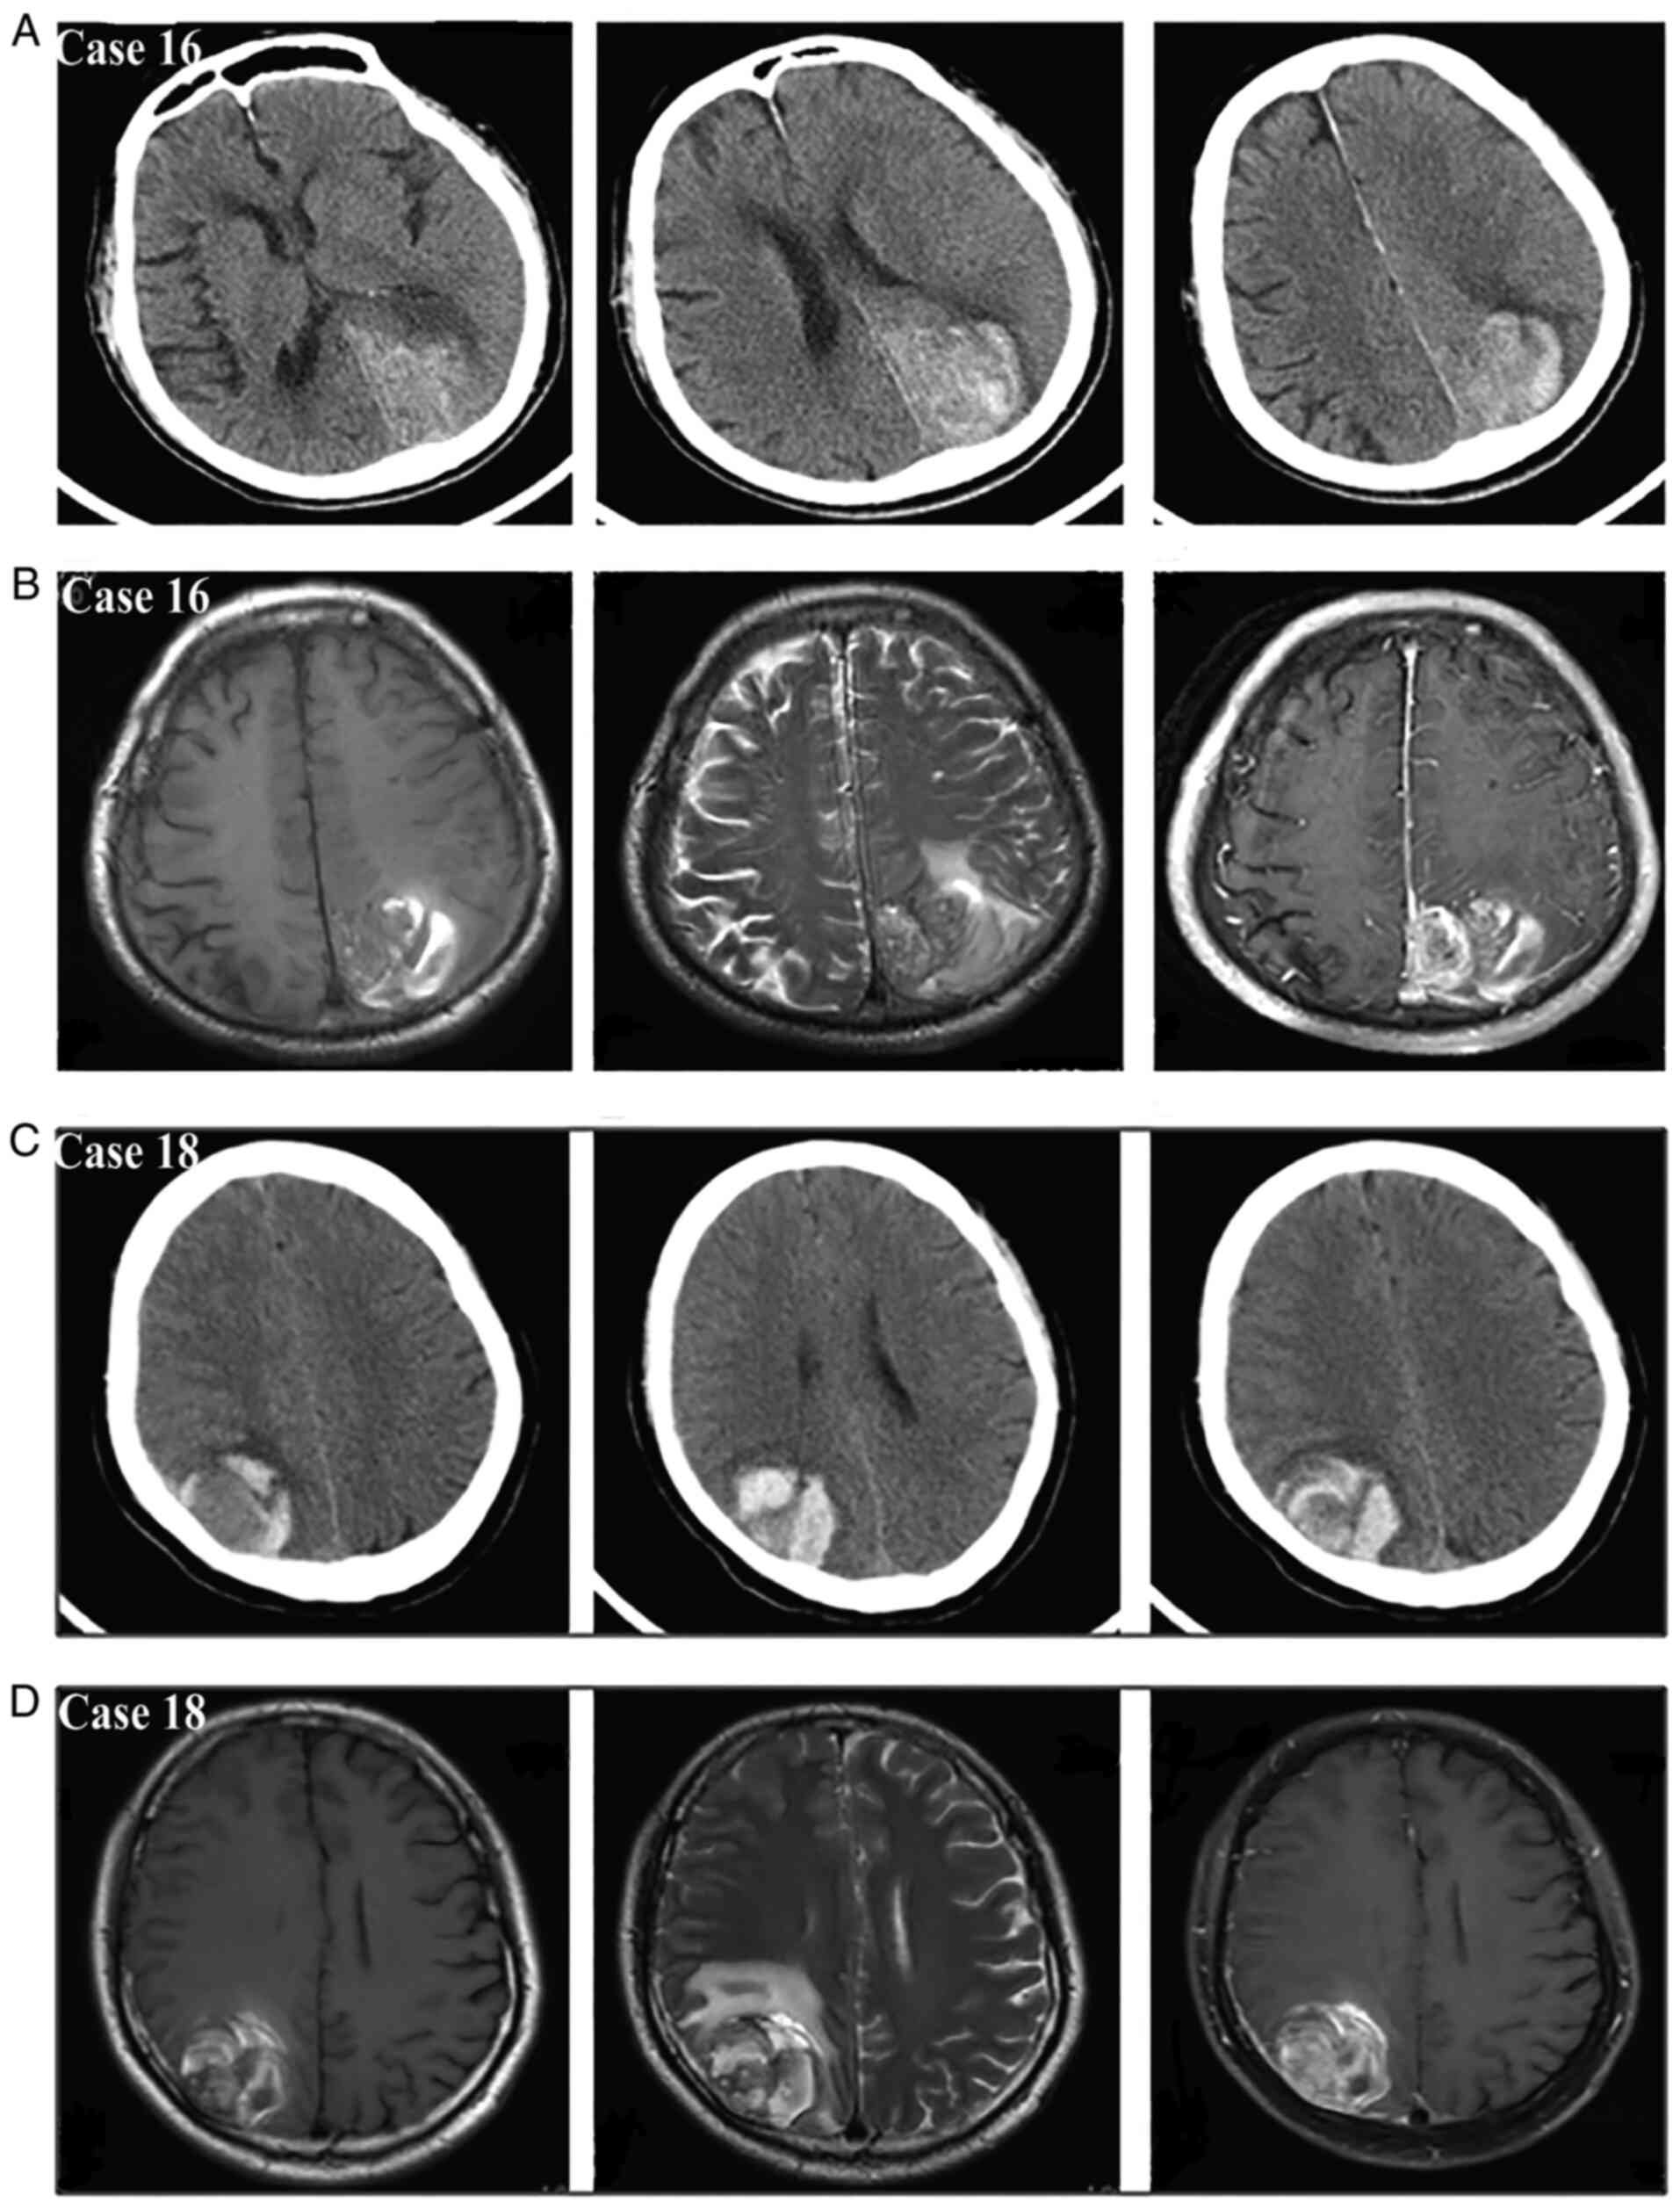

Meningiomas are the most common benign intracranial tumors and frequently present with a gradual onset of neurological deficits; conversely, their acute presentation with hemorrhagic onset appears to be a rare event. Nonetheless, as early surgical evacuation is the foundation of treatment, a timely diagnosis of this rare type of intracranial hemorrhage is necessary. The purpose of the present single‑center study was to investigate the radiological characteristics and propose a new bleeding classification for guiding the diagnosis and treatment. A total of 19 patients consecutively diagnosed with hemorrhagic meningioma were enrolled in this retrospective study. Intracranial extra‑axial mass, tumor‑associated hemorrhage and peritumoral brain edema were the three main radiological features of the hemorrhagic meningiomas. The site of tumor‑associated hemorrhage included the peritumoral space, subarachnoid space, subdural space, brain parenchyma and/or intratumor region. Based on the anatomical relationship between meningioma and hematoma, the spontaneous hemorrhage stemming from meningiomas was further summarized into three bleeding patterns involving purely intratumoral hemorrhage (type I), purely extratumoral hemorrhage (type II) and combined intra/extratumoral hemorrhage (type III); furthermore, the type III hemorrhage usually came from type I bleeding that extended into the surrounding regions. The symptoms in type I patients were generally mild and early surgery was performed following adequate preoperative evaluations. The symptoms in type II patients were mild in certain cases and moderate to severe in others, so early or emergency surgery was chosen according to the clinical status of the patient. Almost all type III patients had moderate to severe symptoms and these patients usually required emergency surgery. In addition, patients with different bleeding types may have different pathological mechanisms underlying the tumor bleeding. Apart from being convenient for diagnosis, this concise and practical bleeding classification may aid in the selection of the treatment strategy and facilitate the understanding of the associated mechanisms.

Figure 1

Figure 2

Figure 3

Figure 4

Figure 5

Figure 6

Figure 7

Figure 8

Figure 9